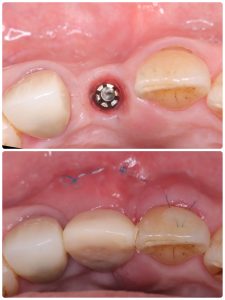

1w前のリムーブに埋入、移植しボリュームアップに根面被覆

生着してるね💪やはりS.B被覆は治癒が早い‼️

既に上皮化している

ネクローシス壊死させるようでは、ダメダメ👎

反省点あり、次回に活かします🤪